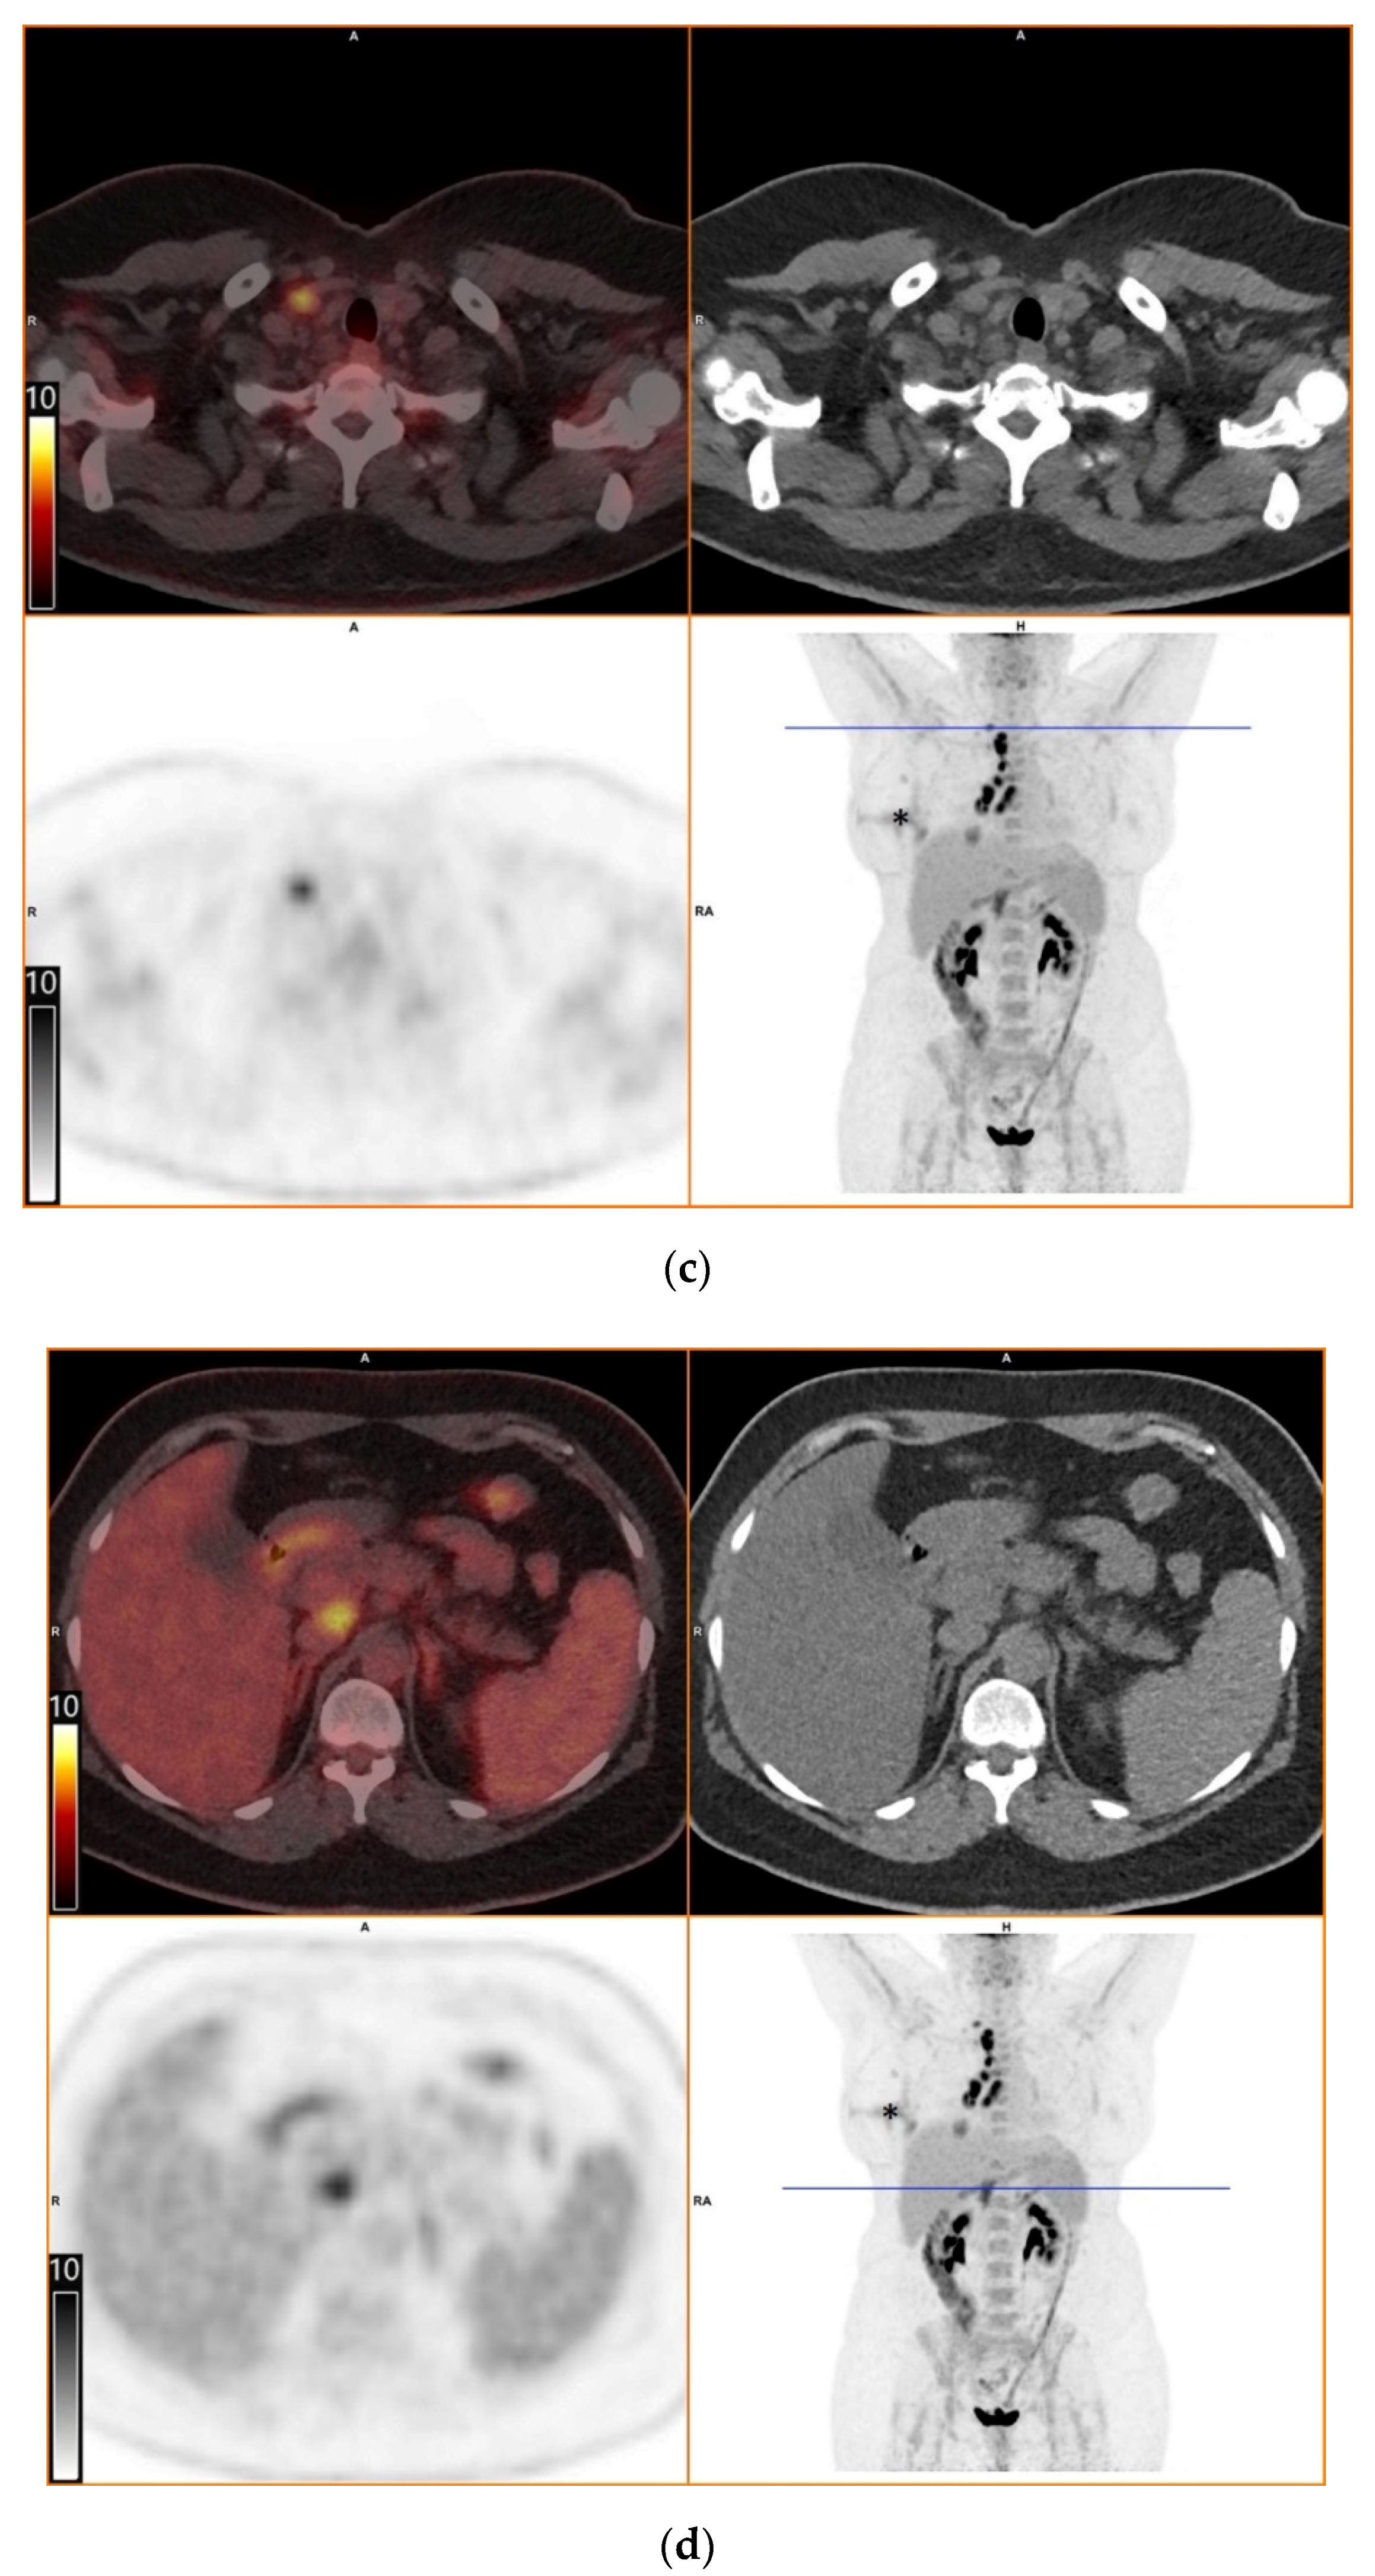

To further evaluate the suspected malignant disease, a [18F]FDG-PET/CT was performed (day +14). It detected multiple hypermetabolic lymph nodes of up to 33 mm in diameter, located right interlobar, at the right hilus, the mediastinum and right supraclavicular. The previously known lesion of the right lung showed only moderate metabolic activity. In addition, a moderately active precaval lymph node was detected (Figure 1).

Figure 1.

[18F]FDG-PET/CT. Upper left: PET and CT fusion images. Upper right: CT images. Lower left: PET images. Lower right: Maximum intensity projection. Blue line: Axial imaging level. Scale bars: Standardized uptake value. Star: Postinterventional diffuse uptake of the right thoracic wall after chest tube placement. (a) Moderate uptake in a solitary solid pulmonary lesion with irregular margins in the right lower lobe of the lung (b) Greater uptake in the draining lymph nodes right interlobar, right hilar and mediastinal (c) A further draining right supraclavicular lymph node showing high uptake as well (d) Moderate uptake in a precaval abdominal lymph node.

The diagnostic contribution of [18F]FDG-PET/CT has been demonstrated in invasive fungal infections, especially in detecting occult foci. [18F]FDG-PET/CT is capable of detecting increased metabolic activity, indicative of inflammatory cell activity, prior to the onset of anatomical abnormalities detectable by conventional radiological means. However, discriminating infection from malignancy and other inflammatory diseases remains difficult [12,13,14]. In our patient, [18F]FDG-PET/CT revealed intense metabolic activity in intrathoracic and supraclavicular lymph nodes. In contrast, the pulmonary lesion in the right lobe displayed only moderate metabolic activity. This finding of equal or greater FDG uptake in draining lymph node(s) in comparison with the associated lung nodule was described by Nagelschneider as “flip-flop fungus sign” (Table 1) with a sensitivity of 60% and specificity of 85% for benign fungal disease, predominately histoplasmosis in a study population from an endemic area [2]. Another approach by Kadaria suggested that dual time point [18F]FDG-PET/CT can be a helpful diagnostic tool for discriminating between benign and malignant lesions in areas endemic for H. capsulatum [15]. The latter radiologic technique was not used in our case. Although useful, [18F]FDG-PET/CT is not recommended in routine diagnostics of fungal infections, mainly due to high costs and generally low availability.

In our opinion, some aspects of the present case need to be addressed explicitly. First, the precaval lymph node with moderately elevated FDG uptake and the concomitant hepatitis remain unexplained but, in retrospect, could be attributed to hepatic involvement in histoplasmosis, which may occur in immunocompetent patients on rare occasions [16]. Second, the negative serological and molecular markers in our patient may be explained by the delay in diagnosis to a time when the infection was already resolving, the poor sensitivity of these tests in non-disseminated disease and the intermittent immunosuppressive therapy with corticosteroids. Third, the initial histopathologic evaluation of the resected lymph nodes with Ziehl-Neelsen, PAS and Giemsa stains revealed necrotic granuloma but failed to identify a fungal pathogen. Although certain phases of H. capsulatum can be visualized by these stains, silver stains, such as Grocott’s methenamine silver stain, are considered the most reliable for the detection of H. capsulatum [7,17,18]. Of note, silver stains may be falsely negative in cases with very few fungal organisms. Fourth, the absence of fungal organisms in the primary CT-guided core needle biopsy of the pulmonary lesion was most likely due to a sampling error. The finding of organizing pneumonia in the biopsy, which often surrounds necrotic lesions, supports this assumption.

Overall, this case stresses the importance of obtaining a careful travel history in a country where histoplasmosis is extremely rare and radiological findings can be mistaken for more common disorders, like malignant or autoimmune diseases. It also highlights the importance of knowledge about possible imported infectious diseases for effective diagnostics. With this case report, we also add further images to the limited database on [18F]FDG-PET/CT findings in patients with histoplasmosis and illustrate the potential diagnostic value of the “flip-flop fungus sign”.